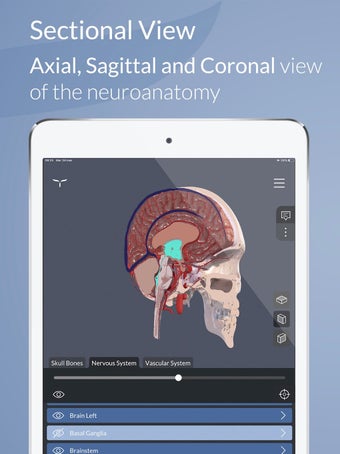

Esta es una aplicación de aprendizaje gratuita, diseñada para ayudarte a entender el cerebro humano y su anatomía y funciones.

Para ayudar en el aprendizaje y la memorización, la aplicación incluye una vasta colección de textos científicos divididos en tres niveles cognitivos, que van desde una visión general hasta definiciones altamente detalladas.